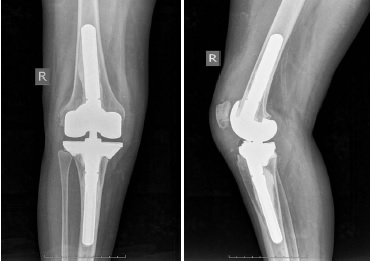

Preoperative planning and implant production

Multislice spiral computed tomography (CT) with 1 mm-thick slices and full-length X-rays of lower extremities (Full Leg Full Spine — FLFS) were taken at the first stage in order to produce custom-made implants. Then a three-dimensional computer model of the knee joint was created. It was followed by the simulation of the bone defect surface with the use of cut and crop tools that allowed to remove artifacts and hypertrophic scars visualized as bone structures. Afterwards the 3D model of the proximal part of the tibia and/or distal part of the femur of the intact (contralateral) joint was mirrored with its following precision positioning to the place of the bone defect in order to replace the latter. Then the Boolean substruction operation was carried out to produce 3D model of the custom-made implant. Pores were made on the implant surface for better osteointegration. The following topologic 3D implant refinement was performed using the SIMP method (Fig. 1). Finally, the implant was 3D printed using Titanium-Aluminium-Vanadium (Ti6Al4V) alloy and sterilized.

Fig. 1. The stage of computer modeling of an individual implant for the replacement of the distal femur (а) and proximal tibia (b) bone defect